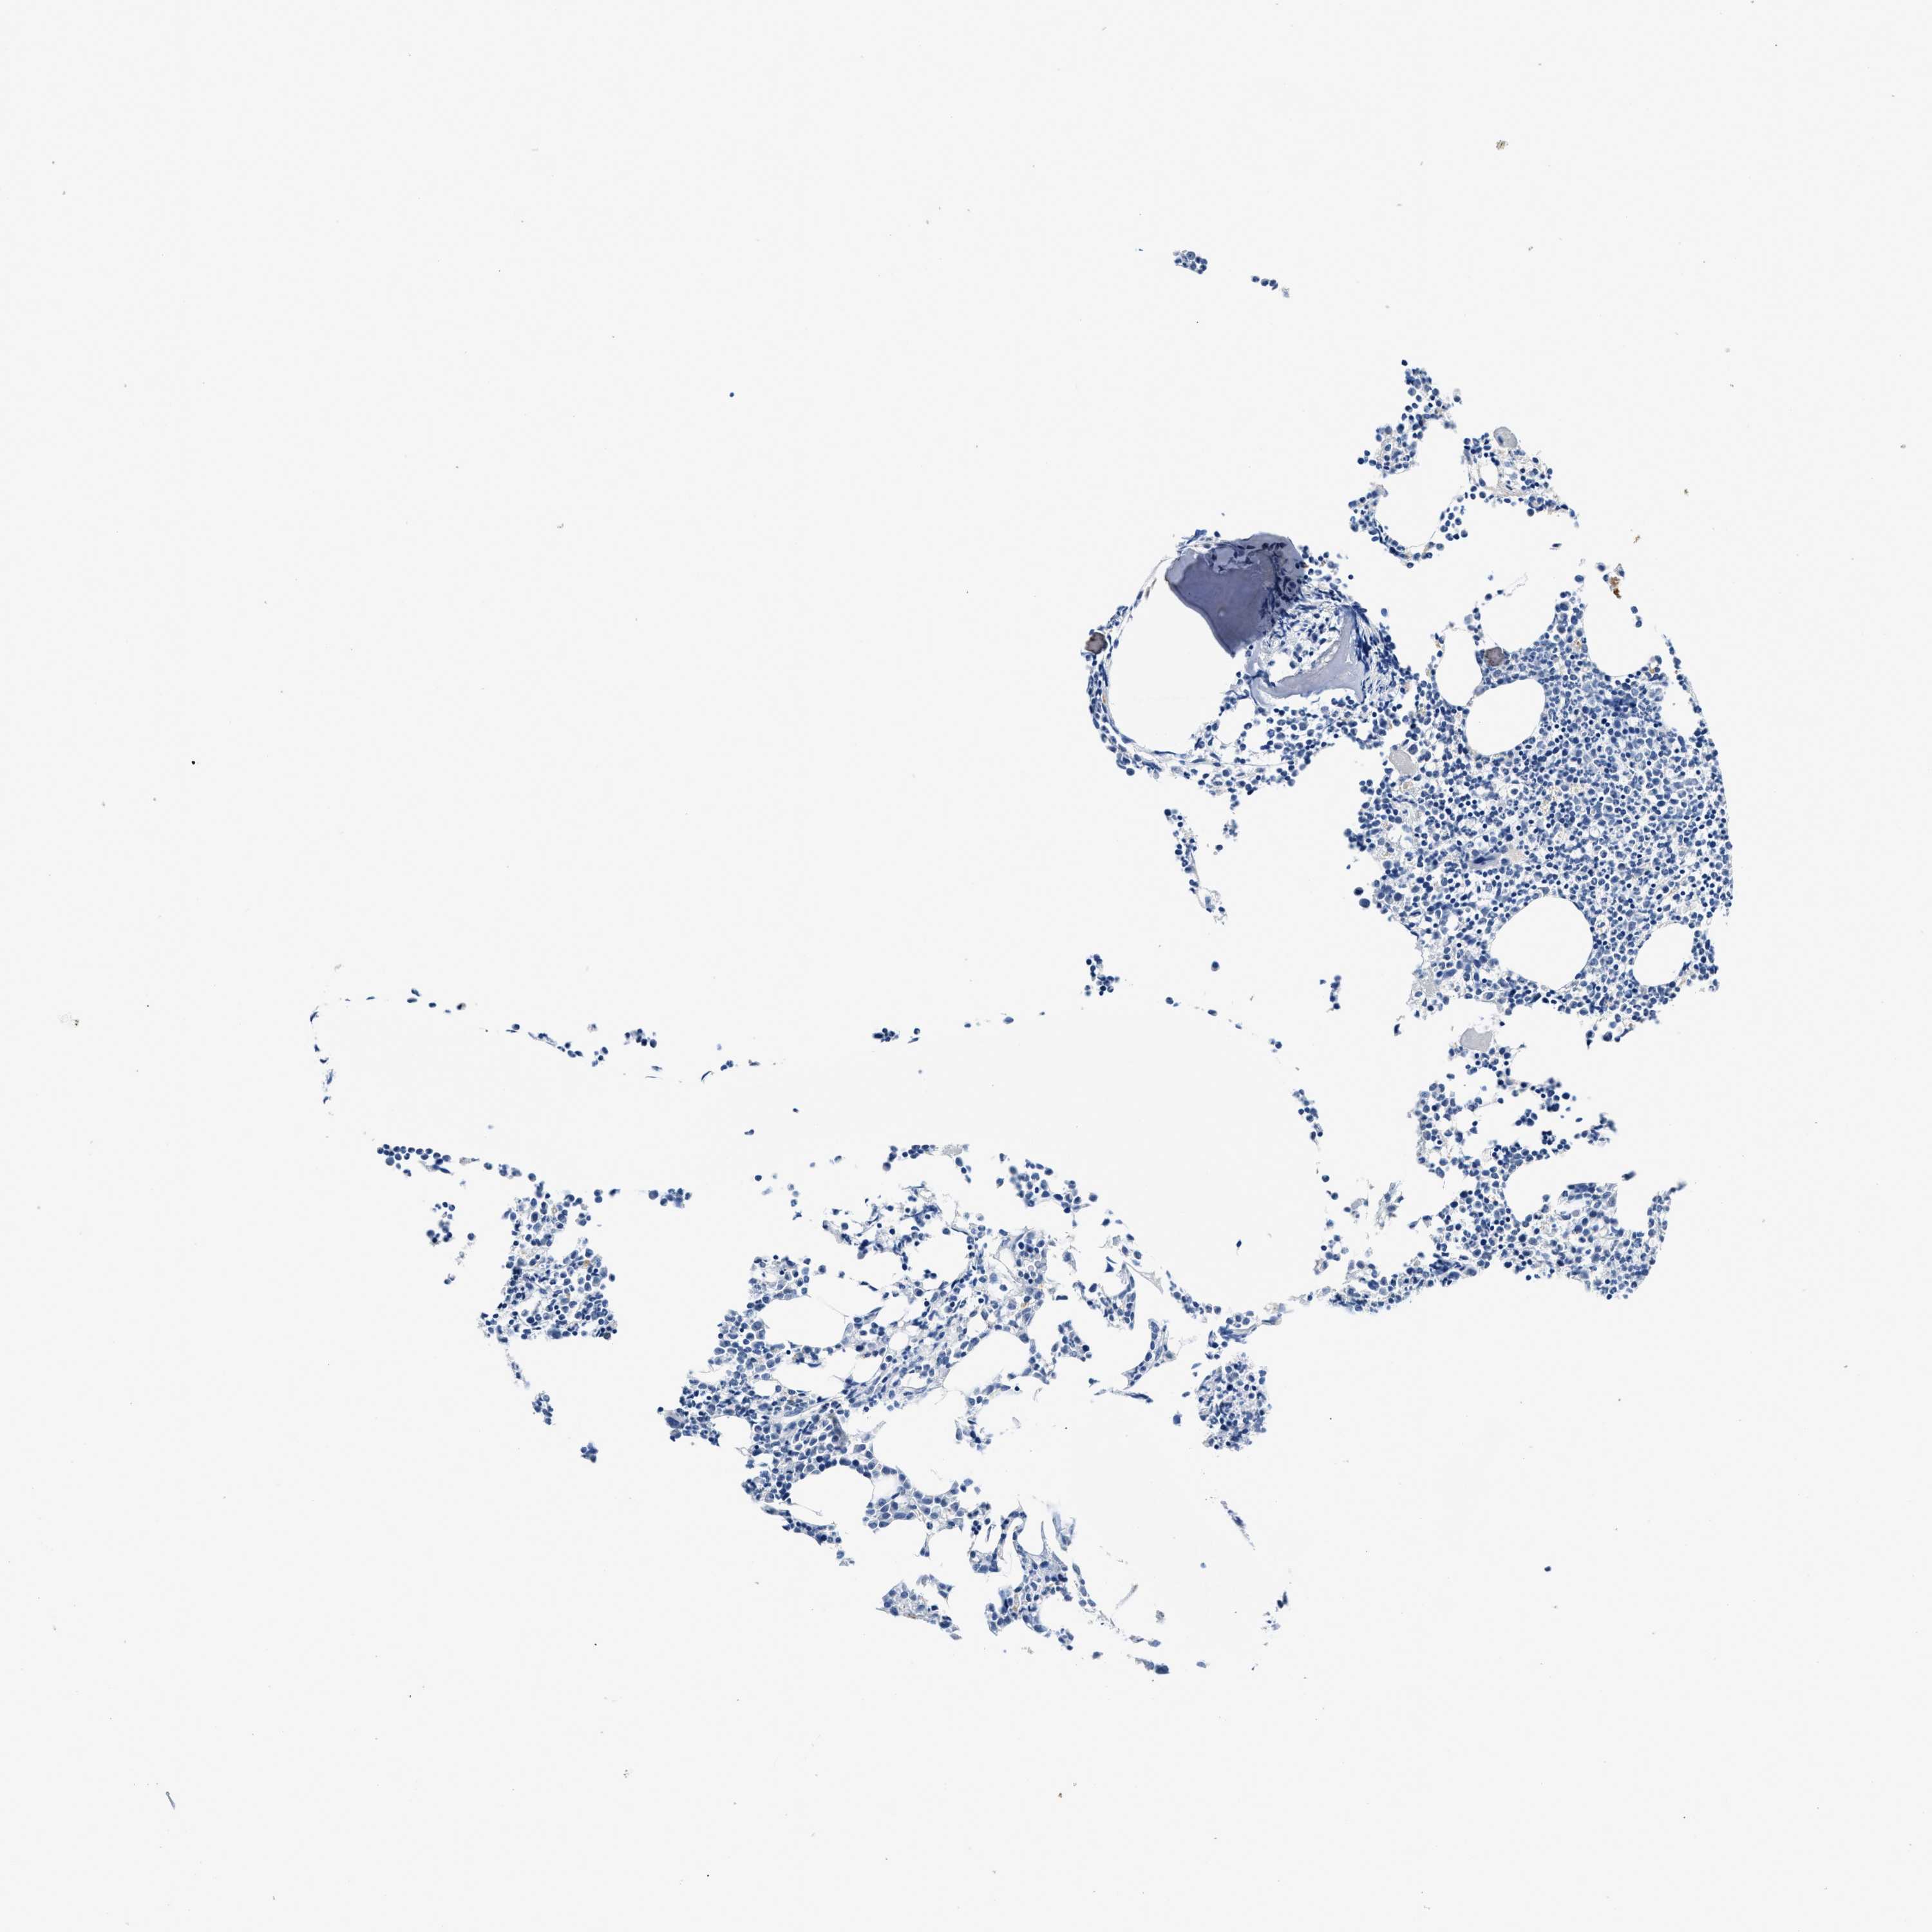

BONE MARROW - Antibody stainingi

Antibody staining in the annotated cell types in the current human tissue is reported as not detected, low, medium, or high, based on conventional immunohistochemistry profiling in selected tissues. This score is based on the combination of the staining intensity and fraction of stained cells.

Each image is clickable and will lead to virtual microscopy that enables deeper exploration of all samples and also displays staining intensity scores, fraction scores and subcellular localization as well as patient and tissue information for each sample.

Antibody HPA019141Antibody CAB000047

Hematopoietic cells LowNot detected